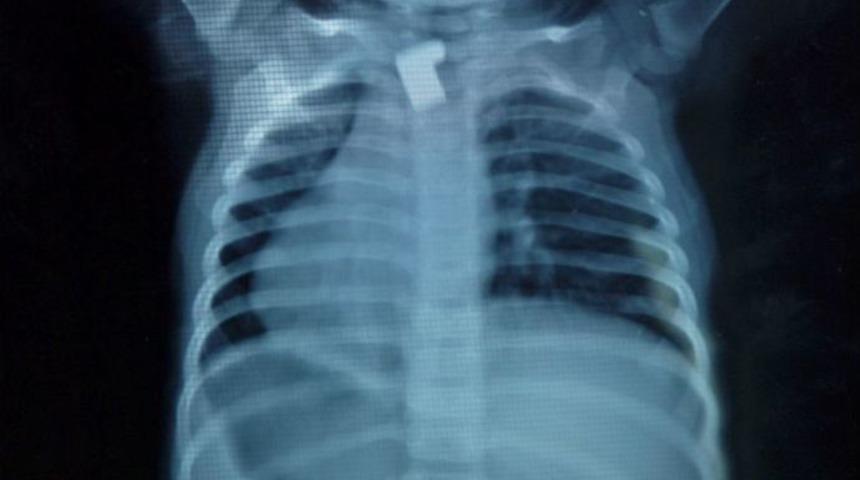

Kardeşinin haber vermesiyle durumdan haberdar olan aile, çocuğu hemen Elbistan Devlet Hastanesi Ana Çocuk Sağlığı Merkezi’ne getirdi. Hastanenin Çocuk Hastalıkları Uzmanı Opr. Dr. Ünal Adıgüzel, küçük çocuğun filminin çekilmesini istedi. Çekilen filmde çocuğun boğazında anahtar parçası olduğu görüldü. Yapılan tahlillerin ardından çocuk ameliyata alındı. Yaklaşık 20 dakika süren bir operasyonda özel aletler marifetiyle anahtar parçası çıkarıldı. Hastanede kontrol altında tutulan Üzeyir Balıkçı, öğle saatlerinde taburcu edildi.

Opr. Dr. Ünal Adıgüzel, “Hastamız 1,5 yaşında. Kırık bir anahtar parçasını, anahtarın uç kısmını yutma şikayetiyle müracaat etti. Çektiğimiz filmde anahtar parçasının yemek borusuna takılı olduğunu tespit ettik. Operasyonla yemek borusundan çıkarttık.” dedi.